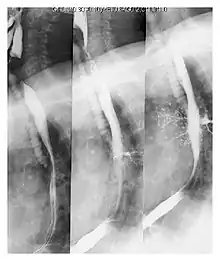

Upper gastrointestinal series at the level of the esophagus, showing pulmonary aspiration of the radiocontrast agent | |